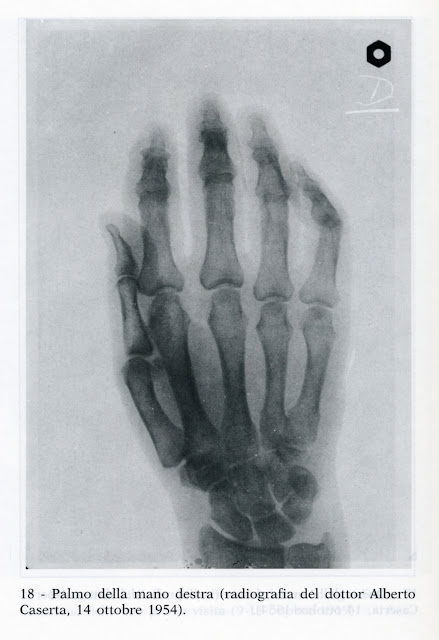

Padre Pellegrino: “Durante la última misa, de las manos del Padre Pío cayeron dos costras, casi perfectamente blancas.

Padre Carmelo, superior del convento: “Los últimos dos o tres meses de vida, las heridas se cerraron lentamente, con una disminución en la cantidad de sangre descargada. A su muerte, la herida se curó por completo sin dejar rastro de cicatrices.

Dra. Rina Giordanelli: “Los últimos meses durante la misa noté que el dorso de las manos del Padre Pío se volvió blanco y liso. La palma de las manos era rosa. Seguí diciéndole a Dios: "¿Por qué sanaste sus heridas?"

El Padre Giacomo Piccirillo da Montemarano tomó fotos de las heridas. Las manos, los pies, el costado no tenían más heridas. La piel era completamente normal. No había signos de cicatrices.

Padre Giacomo: “El Padre Carmelo, el superior, me ordenó tomar la cámara e ir a la celda # 1. Eran aproximadamente las 2:40 AM cuando tomé las fotos. El superior descubrió los sitios de las heridas y comencé a disparar. Me sorprendió que no hubiera heridas. La cámara que tenía era una Kodak plus X pan. Luego quité la película y se la di al padre superior.